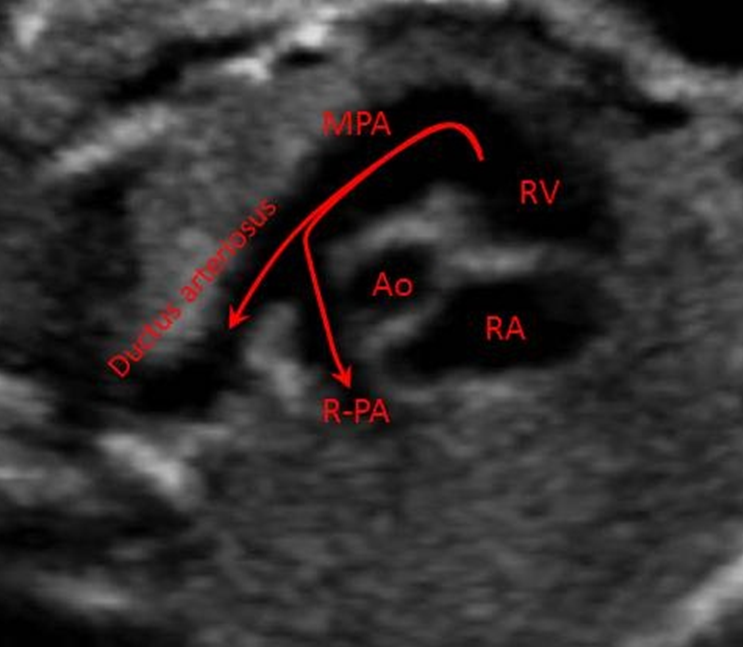

What vessels are imaged?

ductal arch